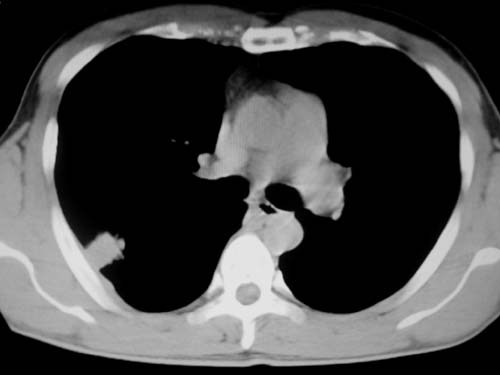

标题: CT19540: 31岁。自述结核性胸水治疗两个月后,在外院拍x线发 [打印本页]

标题: CT19540: 31岁。自述结核性胸水治疗两个月后,在外院拍x线发

右侧胸壁结节状软组织影伴相应肺叶内受侵,伴右侧胸腔积液。考虑:结核性可能大。

支持 右侧胸壁结节状软组织影伴相应肺叶内受侵,伴右侧胸腔积液。考虑:结核性可能大。

1、炎性病变,结核可能;2、右侧少量胸膜积液。

右侧胸壁结节状软组织影伴相应肺叶内受侵,伴右侧胸腔积液,结合临床,首先考虑结核。

考虑结核性胸膜炎,胸膜肥厚,不除外胸膜间皮瘤可能,建议复查。

1)考虑右侧结核性胸膜结节。2)右侧胸膜增厚+包裹性胸腔积液。

结核性脓胸、肺内结核?